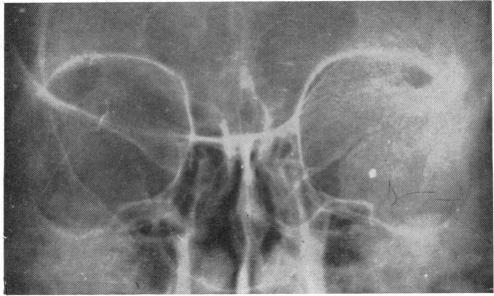

FIBROUS DYSPLASIA OF THE ORBITAL BONES.

Br J Ophthalmol. 1961 Nov;45(11):737-40. doi: 10.1136/bjo.45.11.737.